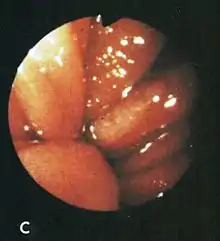

After aspirating some air through the endoscope, this lesion was seen rubbing against opposite folds at the diaphragm level on respiration.

Based on their surgical observations, Windsor and Collis in 1967[4] proposed that blood loss was due to local trauma to the stomach where it rides to and fro in the hiatus on respiration. Boutelier et al.[8] noted on gastroscopy ulcers and erosions at the level of the neck of the hernia in individuals with acute and chronic bleeding, but no detailed description was given. Cameron and Higgins in 1986[1] described linear gastric erosions, later called "Cameron lesions", in people with x-rays showing one-third or more of the stomach above the diaphragm.[9][10][11][12][13][14][15] (figure 1). Over 6 years, Cameron and Higgins studied 109 persons with large hiatal hernias, 55 with anemia and 54 without anemia, at esophagogastroduodenoscopy. Cameron lesions, often multiple, were found at or near the level where the herniated stomach was constricted by the diaphragm. The lesions were typically white, superficial, linear, and oriented along the crests of inflamed appearing mucosal folds (figure 2). Small amounts of blood were often seen on the lesions (Fig 3). Mucosal folds at the diaphragm level were often seen rubbing against each other on respiration (Fig 4). It was proposed that the lesions were caused by mechanical trauma at the level of constriction by the diaphragm [1] Cameron lesions were found in 42% of persons with anemia compared to 24% in those without anemia, a statistically significant difference, p<0.05. Spots of fresh or clotted blood were seen on the lesions in 25% of persons with anemia compared to 7% without anemia, also a significant difference, p<0.05. In the 109 persons in this study, 15 had reflux esophagitis, 11 had peptic ulcers, and 7 had Barrett's esophagus, but none of these findings correlated with anemia. Thus, in people with large hernias, Cameron lesions with evidence of slow bleeding were associated with iron deficiency anemia.